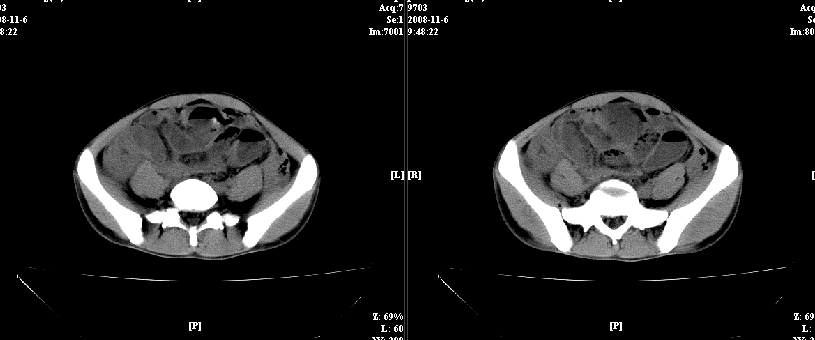

以下是引用dxm在2008-11-6 13:32:00的发言:[br]膀胱直肠窝积液 盲肠璧增厚 小肠淤积

以下是引用zsl6918在2008-11-6 14:13:00的发言:[br]如果阑尾炎病史明确,那腹腔及盆腔改变考虑脓肿形成.

以下是引用zjzjr在2008-11-6 14:37:00的发言:[br]支持阑尾炎伴盆腔及右髂窝脓肿形成